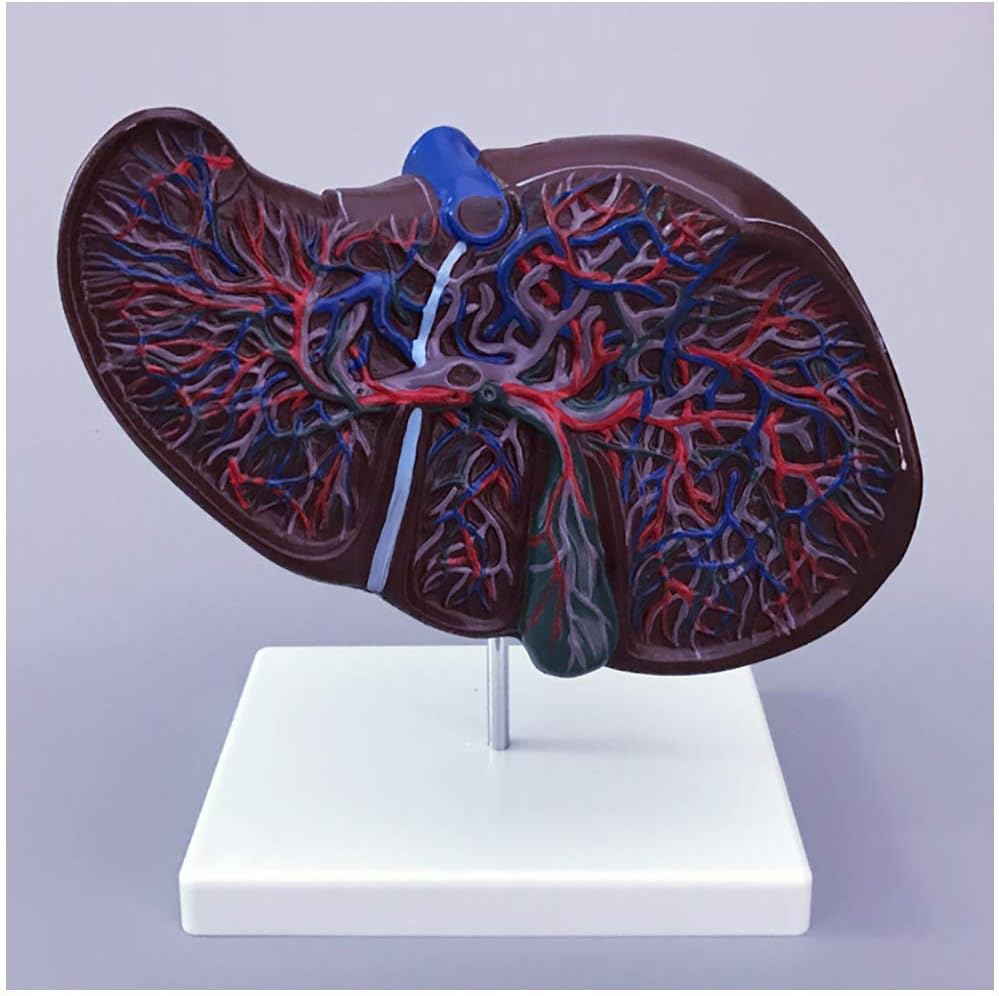

- 食品グレードのPVC環境に優しい素材で作られ、コンピューターカラーマッチング、高級手描き。人間の肝臓構造をほぼ忠実に表示します。正確かつ効果的な実践的な学習教材を提供します

- 教育ツール: さまざまな位置を区別するためにさまざまな色が使用されており、色は明るく生徒の注意を引きやすいため、生徒の理解を促進し、教室での授業のデモンストレーションを行うことができます。

- このモデルは、より正確な学習を行うために、色を使用して血管、門脈血管、肝内および肝外胆管のネットワークのさまざまな部分を区別します。したがって、この直感的な教育を効果的な理論的理解に使用して、関連する知識を深く明確に習得することができます。

このモデルは、肝臓の血管の完全なネットワークをさまざまな色で表します: 門脈血管、肝内胆管、肝外胆管、ベース上に配置されています。ディスプレイや光環境の違いによる色の違い。